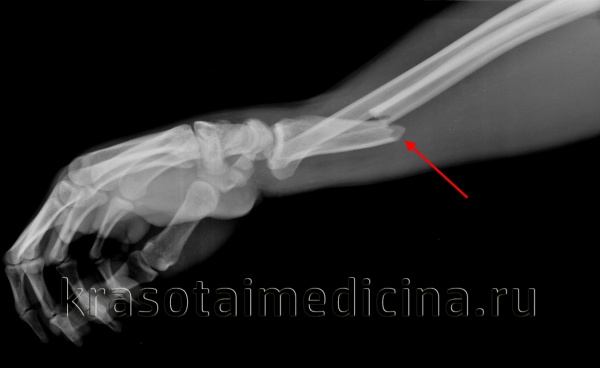

Предплечье над лучезапястным суставом отечно, синюшно, деформировано, резко болезненно при прощупывании и осевой нагрузке. При сопутствующем повреждении ветвей срединного и лучевого нерва выявляются нарушения чувствительности, ограничение движений четвертого пальца. При переломах лучевой кости без смещения на руку накладывают лонгету сроком на 3-4 недели. При переломах со смещением предварительно выполняется репозиция (обычно – ручная, реже – аппаратная), после чего накладывается гипс сроком на 4-5 недель. При повреждениях нервов пациентам назначают тиреокальцитонин, анаболические гормоны, неостигмин и витамины группы В.

- Рентгенография. Является основным инструментальным методом. Для уточнения диагноза при изолированных переломах назначают рентгенографию предплечья в двух проекциях. При переломах Монтеджи выполняют рентгенографию предплечья с захватом локтевого и лучезапястного сустава, используя две стандартные и косую проекцию.